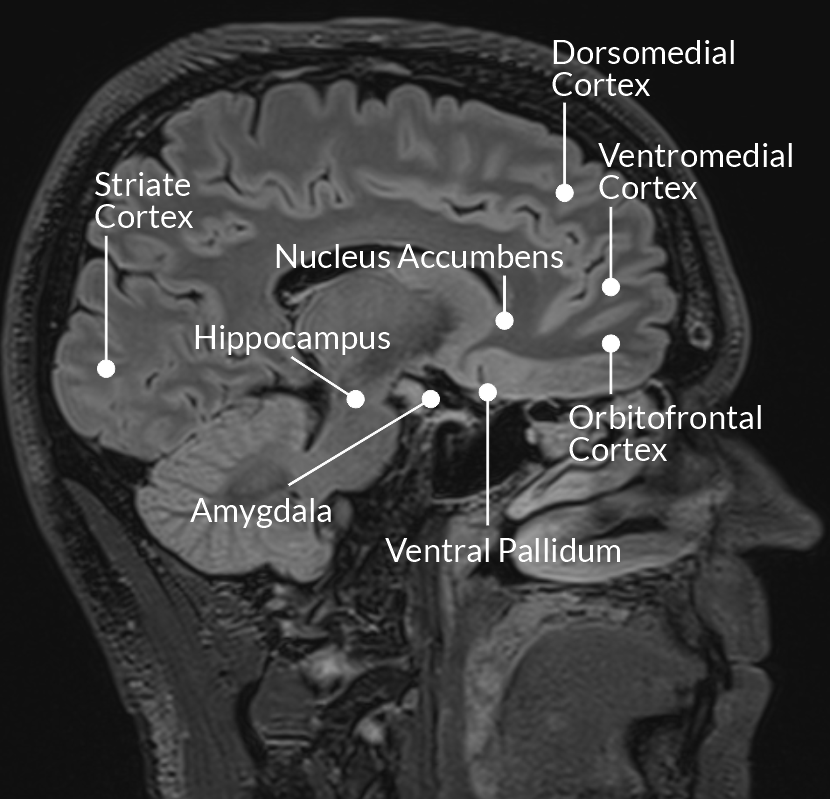

Ihmisaivot ovat kehittyneet vaihe vaiheelta miljoonien vuosien aikana sellaisiksi kuin ne ovat tänä päivänä. Kehityksen ensimmäinen vaihe vastasi elintärkeistä toiminnasta, kuten hengityksen, sydämen sykkeen ja perusliikkeiden ohjaamisesta, ja sen voidaan arvioida tapahtuneen noin 500 miljoonaa vuotta sitten. Seuraavien 250 miljoonan vuoden aikana aivoihin kehittyi uusia alueita, jotka mahdollistivat tunteiden kokemisen ja säätelyn sekä motivaatiokäyttäytymisen1.

Näiden kaikille eläimille ominaisiksi luonnehdittavien toimintojen päälle kehittyi aivojen uusin ja kehittynein osa, aivokuori. Aivokuori vastaa korkeamman tason kognitiivisista toiminnoista, kuten kielestä, ongelmanratkaisusta ja tiedon käsittelystä. Se on noin seitsemän miljoonan vuoden ikäinen, ja sen viimeisin merkittävä "päivitys" tapahtui noin 50 000 vuotta sitten2.